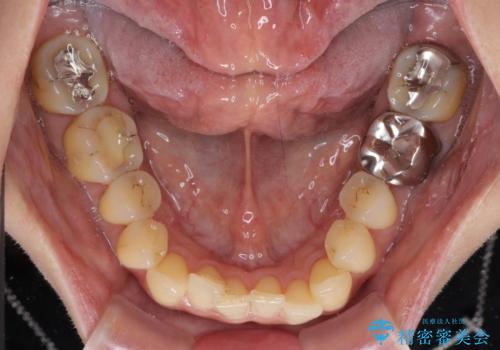

- 前歯のクロスバイトが気になり、インビザラインによる矯正治療を希望して来院された患者様です。

インビザラインで歯列を移動する前に、上顎前歯をワイヤー矯正で整え、その後上下歯列をインビザラインにて矯正治療を行うこととしました。